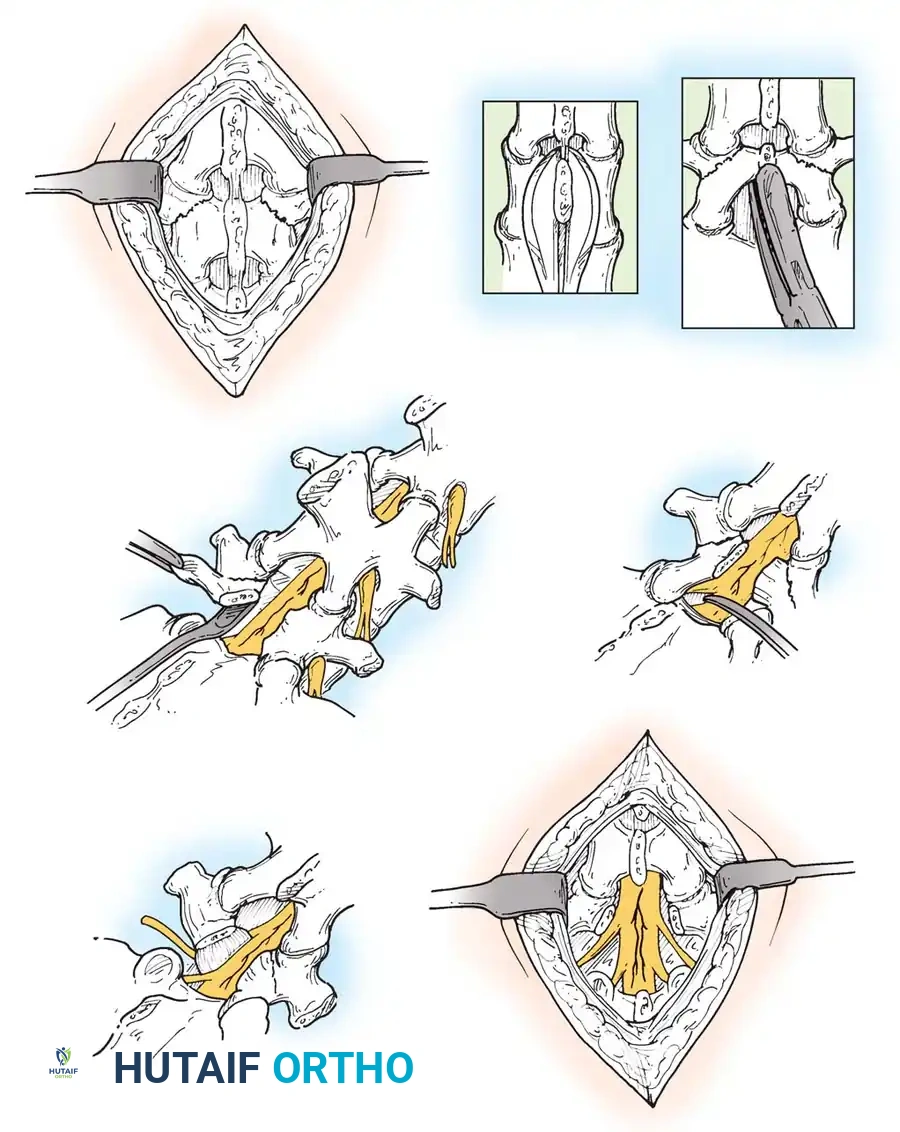

Historically, the Gill procedure involved the isolated removal of the loose posterior lamina (the "Gill fragment"). However, due to the high risk of iatrogenic instability, this is now universally combined with instrumented fusion.

- Exposure: A standard midline incision is made. Subperiosteal dissection exposes the spinous processes, laminae, pars defects, and transverse processes of the affected levels.

- Decompression: The loose lamina and spinous process are carefully excised. The fibrocartilaginous mass at the pars defect is meticulously resected using Kerrison rongeurs to decompress the exiting nerve root (e.g., L5 root) throughout its course in the neuroforamen.

- Instrumentation: Pedicle screws are placed under fluoroscopic or navigation guidance. The trajectory must account for the altered anatomy; the L5 pedicle in isthmic spondylolisthesis is often dysplastic and sclerotic.

- Grafting: The transverse processes and lateral gutters are decorticated with a high-speed burr. Autologous local bone graft, supplemented with allograft or orthobiologics, is packed into the posterolateral gutters to facilitate fusion.

- Facetectomy: A unilateral (TLIF) or bilateral (PLIF) facetectomy is performed to gain access to the disc space while minimizing neural retraction.

- Discectomy and Endplate Preparation: A thorough annulotomy is performed. The disc material is evacuated using pituitary rongeurs and curettes. The cartilaginous endplates are scraped to expose bleeding subchondral bone, ensuring a robust fusion bed.